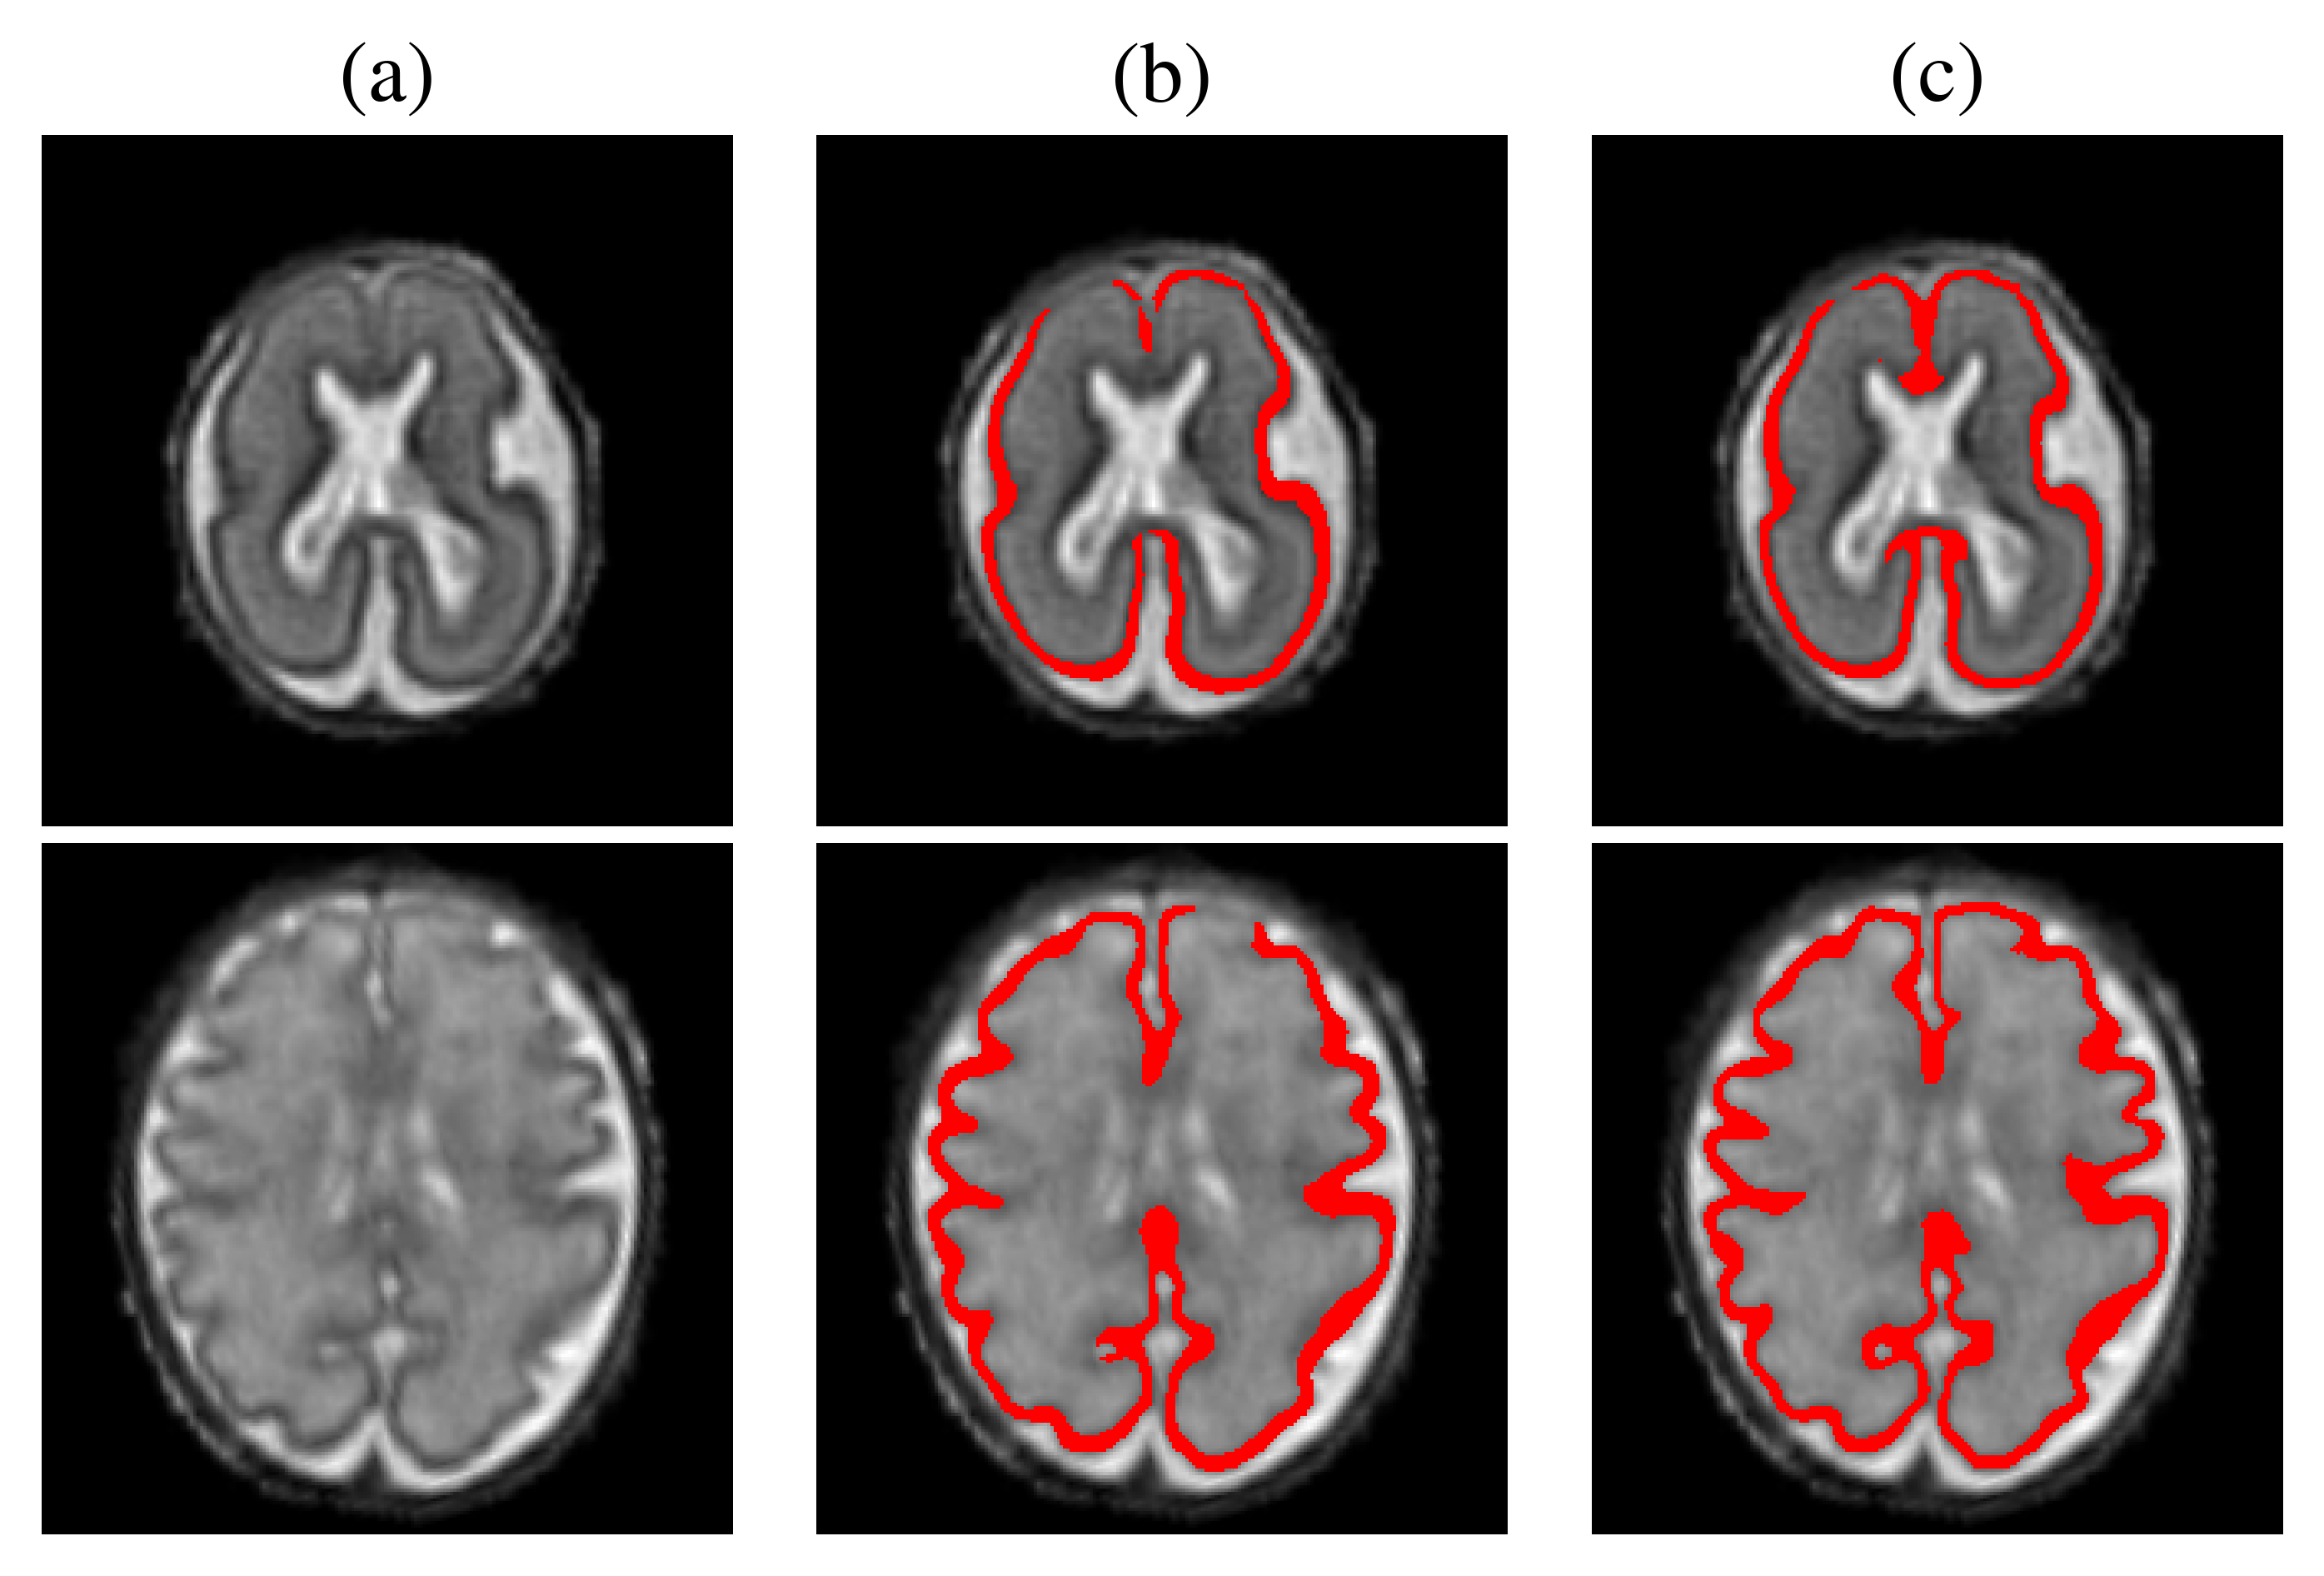

Fig. 4: Segmentation results on 23 (top) and 32 (bottom) gestational weeks fetuses: (a) T2w SR image; (b) Baseline U-Net (c) and TopoCP.

Figure 2 shows the GT of two representative patches with their predicted likelihood and segmentation overlaid on the T2w SR image. These results illustrate the benefits of TopoCP on the estimated probability maps, detecting more subtle variation of the cortex. The improved likelihood echoes with a better segmentation. A summary of the performance metrics on the fetal brain atlas is presented in Table 2. TopoCP outperformed the Baseline U-Net in all evaluation metrics (highlighted in bold in the table). Corrected p-values between both methods are shown in italic, indicating that our method significantly improves the segmentation. Metrics are shown as a function of the subjects’ gestational age in Figure 3. While the overlap metric constantly improves throughout gestation, error distance and topological metrics improve mainly from the third trimester. We hypothesize this is due to the increased folding patterns of the cortical surface in the last trimester and thus where the topological constraint is more valuable.

The inter-rater reliability showed a good agreement of 74%. Table 3 shows the consensus of the experts’ blind evaluation of the cortical plate segmentation on SR volumes based on T2w clinical acquisitions. For both excellent and acceptable sets, TopoCP was selected as giving the best segmentation, showing the robustness of our method to the SR quality. Figure 4 illustrates a representative slice segmented with both methods.